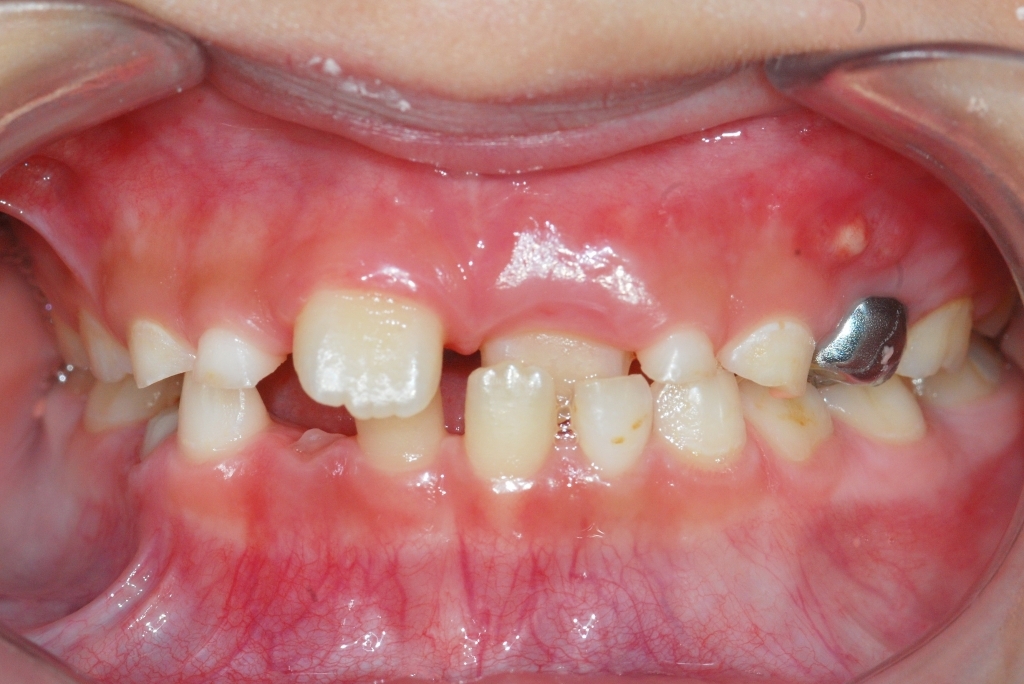

서울보스톤치과에서 치료 받으신 분들의 전후사진입니다.